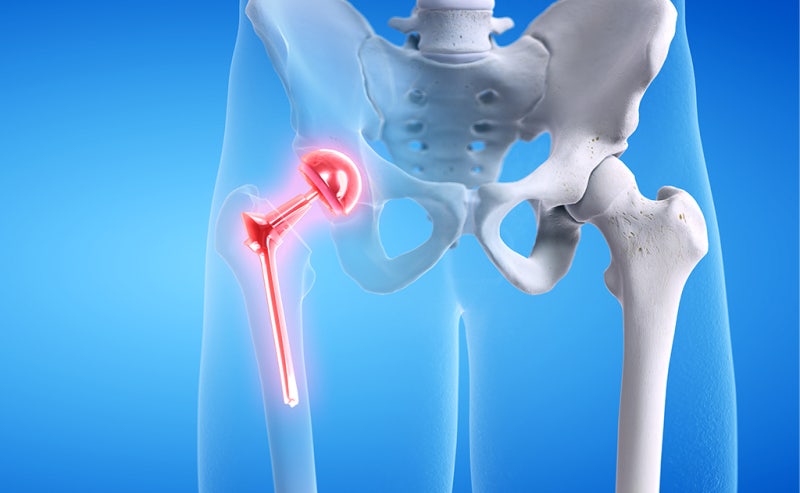

고관절 수술은 다양한 이유로 시행될 수 있지만, 일반적으로는 고관절 관절염, 외상, 또는 선천적인 기형 등으로 인해 통증이나 기능 저하가 나타날 때 이루어집니다. 이 수술에는 인공관절 치환술, 관절경 수술 등의 방법이 있으며, 각각의 수술 방법은 회복 단계와 필요한 시간에 서로 영향을 미칩니다. 고관절 수술의 주된 목적은 통증을 감소시키고, 이동성과 일상생활의 질을 향상시키는 것입니다. 그러므로, 환자는 수술 후 생활 습관을 조절하고, 적극적인 rehabilitative 간호를 통해 빠른 회복을 도모해야 합니다.

- 인공관절 치환술: 가장 일반적인 고관절 수술입니다. 퇴행성 관절염이나 심한 외상으로 인해 고관절이 손상된 경우, 인공 관절로 대체합니다. 이 수술은 대개 1-2시간 가량 소요되며, 회복이 길어질 수 있습니다.